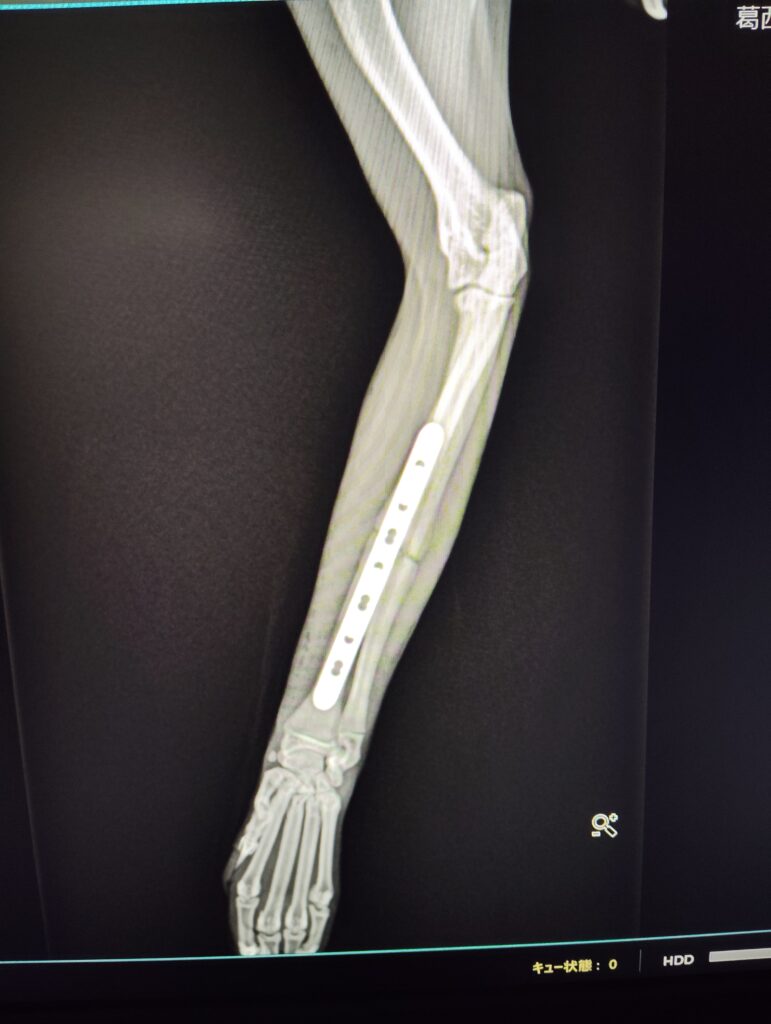

・φ1.5mmのロッキングプレートを使用

術後

3日後圧迫包帯を抜去、早期に着肢を確認